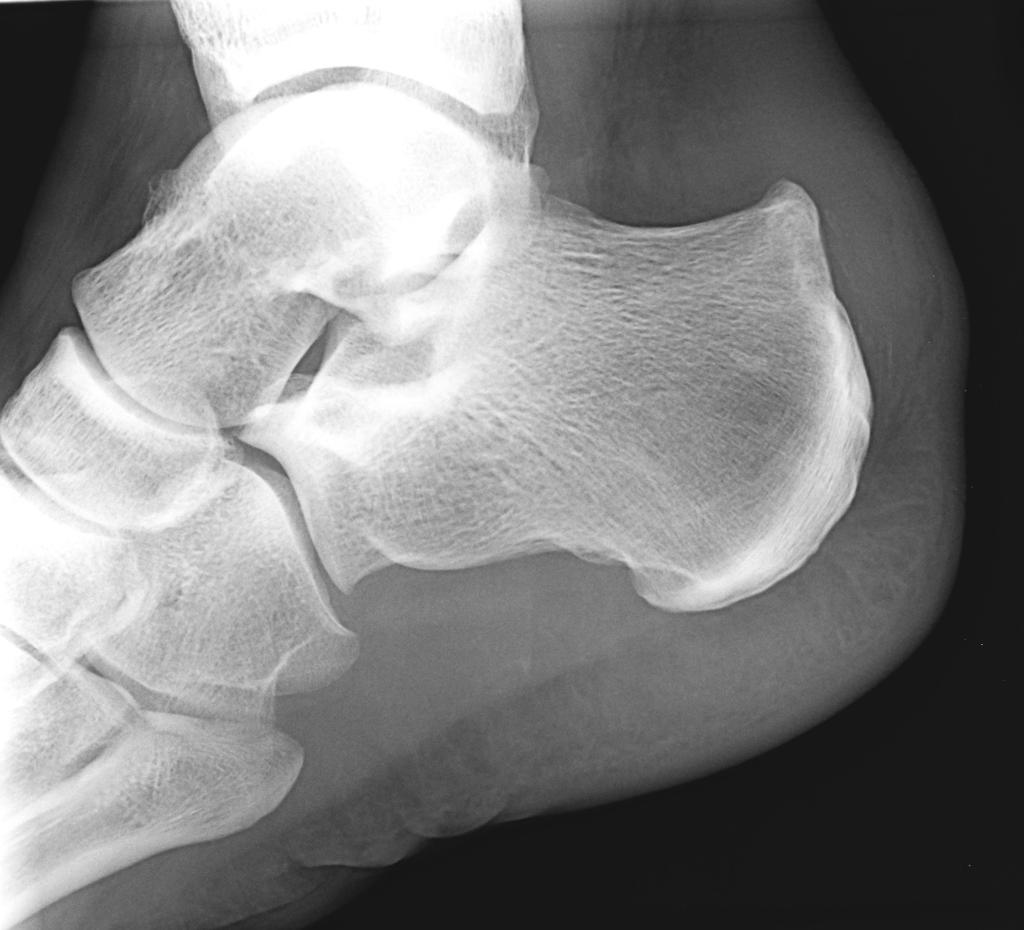

Le pied et la cheville

Le pied et la cheville peuvent être sources de nombreuses pathologies ou blessures, tant chez les sportifs que les non sportifs. Ces blessures empêchent la reprise des activités, tant sportives que professionnelles, source d'impatience et d'anxiété.